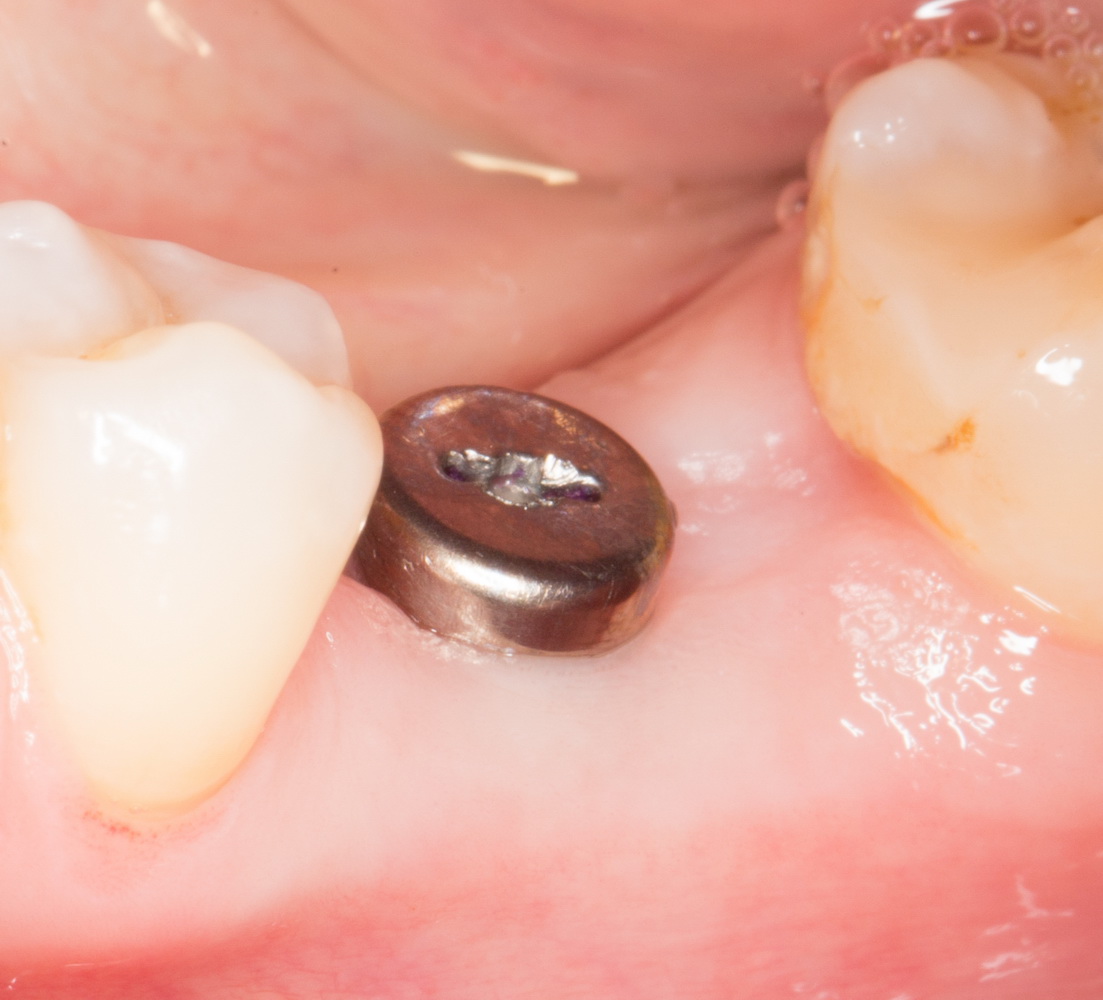

В данном случае мы используем XiVE, что, с одной стороны, несколько сложнее, чем, к примеру, использование погружного импланта, но, с другой — позволяет нам ориентироваться по абатменту TempBase, который входит в комплект поставки и является, одновременно, имплантодержателем:

Временный абатмент/имплантодержатель помогает понять, какую картинку увидит врач-ортопед перед началом протезирования. ИМХО, это очень удобно.

Всё. Имплантат установлен: